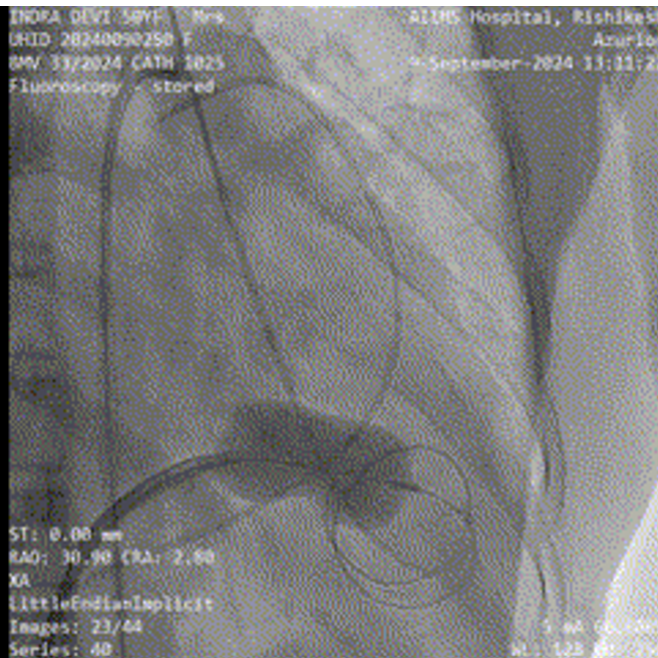

Given prohibitive surgical risk, high-risk BMV was attempted. Bilateral carotid angiography was performed and SpiderFx embolic protection devices (Medtronic, USA) deployed. Under TEE guidance, transseptal puncture was done, and an Inoue balloon (Toray, Japan) was advanced across the mitral valve. Sequential dilatations reduced the mean gradient with no embolic debris in filters. The patient improved hemodynamically and was discharged in stable condition.

The patient was deemed prohibitive risk for surgical mitral valve replacement with clot extraction, so a high-risk percutaneous approach was planned. Bilateral carotid angiography was performed, and 5 mm SpiderFx embolic protection devices (Medtronic, Minneapolis, MN, USA) were deployed to minimize embolic risk. Transseptal puncture was guided by transesophageal echocardiography because of a thin interatrial septum. An Inoue balloon catheter (Toray, Tokyo, Japan) was advanced across the mitral valve, and sequential graded dilatations were performed under fluoroscopy. Mean transmitral gradient fell markedly, with corresponding fall in pulmonary artery pressure. The embolic filters were retrieved without visible debris. The procedure was uneventful, with no neurological events. The patient was extubated on table, remained hemodynamically stable, and reported significant symptomatic improvement. She was discharged in NYHA class II and, at follow-up, was able to resume routine activities with sustained benefit.